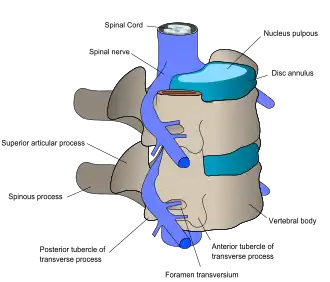

Back structures

The lumbar (or lower back) region is made up of five vertebrae (L1–L5), sometimes including the sacrum. In between these vertebrae are fibrocartilaginous discs, which act as cushions, preventing the vertebrae from rubbing together while at the same time protecting the spinal cord. Nerves come from and go to the spinal cord through specific openings between the vertebrae, providing the skin with sensations and messages to muscles. Stability of the spine is provided by the ligaments and muscles of the back and abdomen. Small joints called facet joints limit and direct the motion of the spine.[33]

An intervertebral disc has a gelatinous core surrounded by a fibrous ring.[35] When in its normal, uninjured state, most of the disc is not served by either the circulatory or nervous systems – blood and nerves only run to the outside of the disc.[35] Specialized cells that can survive without direct blood supply are in the inside of the disc.[35] Over time, the discs lose flexibility and the ability to absorb physical forces.[26] This decreased ability to handle physical forces increases stresses on other parts of the spine, causing the ligaments of the spine to thicken and bony growths to develop on the vertebrae.[26] As a result, there is less space through which the spinal cord and nerve roots may pass.[26] When a disc degenerates as a result of injury or disease, the makeup of a disc changes: blood vessels and nerves may grow into its interior and/or herniated disc material can push directly on a nerve root.[35] Any of these changes may result in back pain.[35]